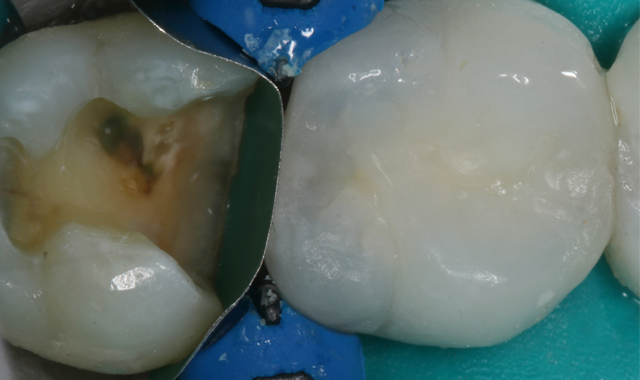

Fig. 3

Fig. 4

The patient was anesthetized and a latex-free dental dam was placed with an NW clamp on the second molar (Fig. 3). Utilizing a Brasseler 6845KR.31.018 diamond, the old composite restoration was removed in its entirety. The deeper portions of the box were beveled with a 6856.018 diamond and the cavosurface margins were beveled to increase enamel bonding area and for esthetics.

Once the preparation was complete, the preparation was micro-abraded with an air abrasion unit (PrepStart™, Danville) with a 90-degree .015 tip and 27-micron aluminum oxide powder. This step results in micro-retentive surface increases, surface area that potentially further increases dentin bonding and reduces post-op sensitivity (Fig. 4).